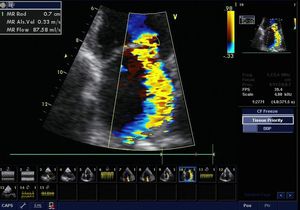

Mitral regurgitation jet on echo

Cardiology

Heart Valve

Mitralvalve